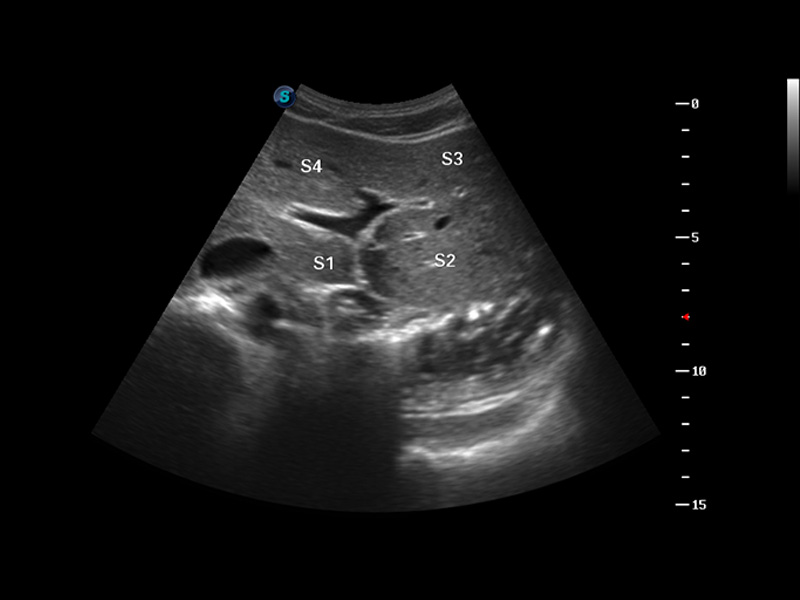

谐波成像

空间复合成像

3D/4D成像